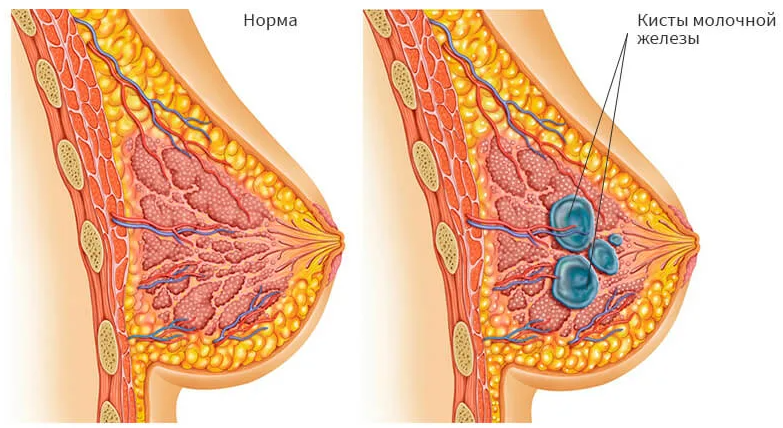

В медицине кистой называется полость со стенками, заполненная жидкостью. В молочной железе она представляет собой мешочек из соединительной ткани. Это доброкачественное образование.

Киста образуется при закупорке молочных протоков и заполнении их жидкостью.

Размер кист начинается от нескольких миллиметров и способен прогрессировать до 3-5 сантиметров.

Они могут быть одиночными или множественными, располагаться группами. Форма образований чаще округлая или овальная, редко - неправильная.

Киста может быть одиночная (солитарная) или множественная (поликистоз). Одно- и многокамерная - по количеству полостей в грудной железе.